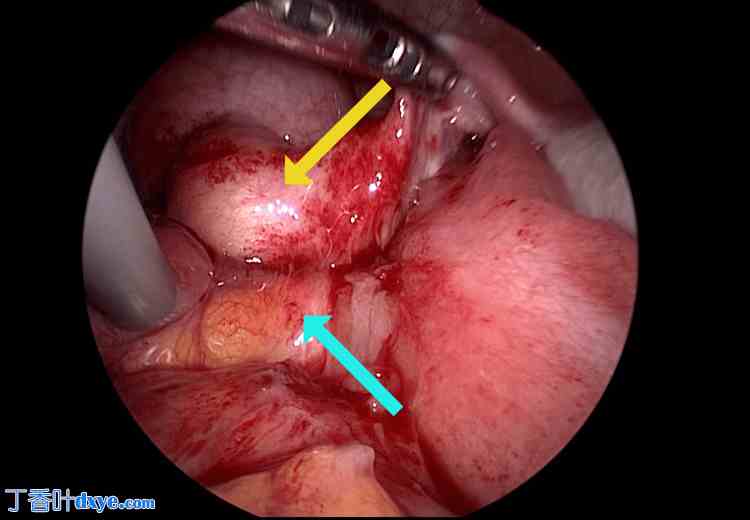

患者在接受全子宫切除术(TLH)后被诊断为阴道阴道炎(VCD)。初始治疗包括抗生素治疗,感染控制后进行再次缝合。入院当天开始经验性给予头孢美唑(2 g/天),疗程7天,阴道培养结果显示为化脓性链球菌。在确认实验室检查结果改善且腹膜刺激症状消退后,于入院第8天行腹腔镜辅助经阴道阴道缝合术。术中,小肠覆盖于阴道残端,并观察到部分阴道残端(黄色箭头)与小肠(浅蓝色箭头)之间存在粘连(图5)。

图5. 阴道残端粘连。